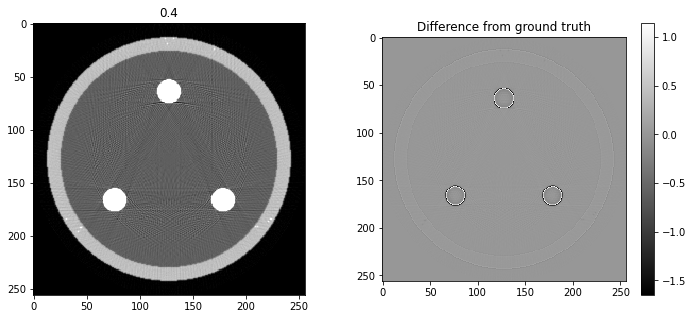

On se propose d’utiliser ce fit polynomial pour corriger l’image. Pour cela, et en première approximation, nous allons supposer que les artefacts observés viennent uniquement des inserts d’iode. Ceux-ci sont reconstruits correctement, avec peut-être une valeur à l’intérieur de l’insert légèrement différente de la vraie valeur, mais en tout cas, ces inserts sont identifiables. Ils sont aussi beaucoup plus intenses que les autres structures de l’image reconstruite.

Questions

- Trouvez manuellement un seuil qui vous permette d’isoler les inserts d’iode dans l’image reconstruite.

- Projetez les valeurs de ces inserts d’iode ; transformez le sinogramme obtenu en utilisant le polynôme trouvé précédemment.

- Reconstruisez une image à partir de ce sinogramme transformé.

- Lancez la boucle d’images suivante : qu’observez-vous ?

# Question 12

search = np.linspace(0,1,11)

for alpha in search:

rec = out+alpha*reproj

f,ax = plt.subplots(1,2,figsize=(12,5))

ax[0].imshow(rec,vmin=0,vmax=0.5)

ax[0].set_title(alpha)

im = ax[1].imshow(img[80]-rec)

f.colorbar(im,ax=ax[1])

ax[1].set_title('Difference from ground truth')

plt.show()